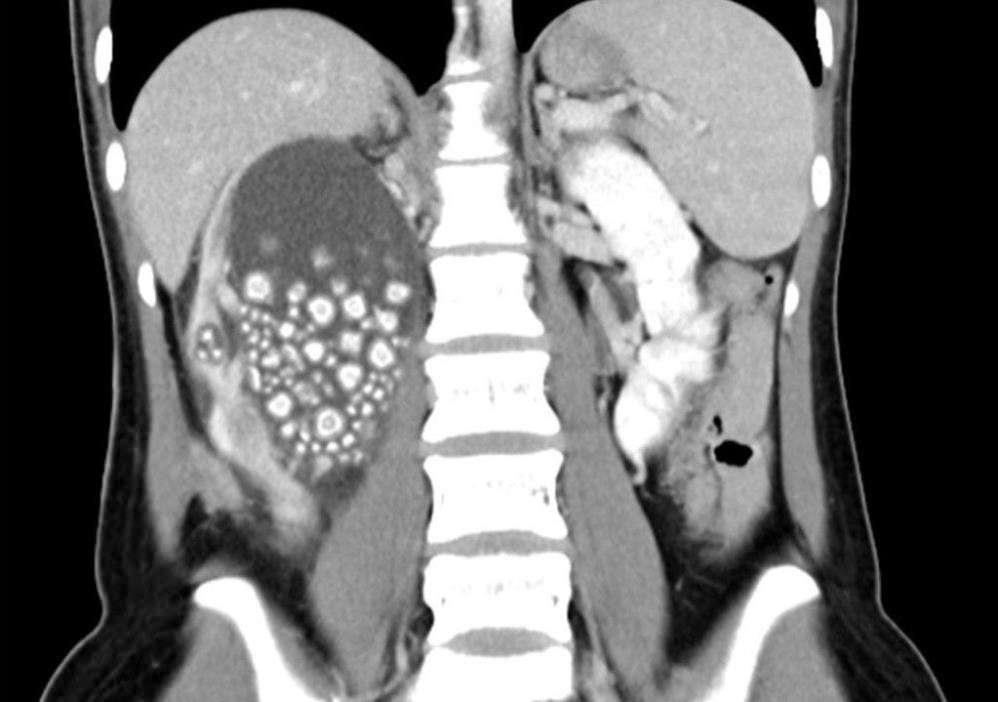

Tayvan'ın güneyinde yer alan Tainan şehrinde 20 yaşındaki Xiao Yu sırt ağrısı şikayetiyle hastaneye başvurdu. Yapılan tetkiklerin sonucunda böbreklerinde çok sayıda böbrek taşı tespit edilen Yu acil ameliyata alındı. Başarılı geçen ameliyatın ardından Yu'nun böbreklerinden 0.5-2 cm boyutlarında 300'den fazla böbrek taşı çıkarıldı.